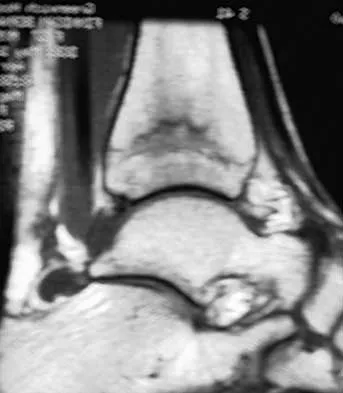

A 30-year-old woman injured her ankle playing soccer 3 months ago. She now reports popping and pain over the lateral side of her ankle. An MRI scan is shown in Figure 33. What structure needs to be repaired to alleviate the popping?

Explanation

The symptoms and MRI scan indicate dislocated peroneal tendons. In this patient, the structure that needs to be repaired is the superior peroneal retinaculum. If the popping was coming from a torn peroneal tendon, repair would involve the peroneal longus or brevis tendon, but this is not shown in the MRI scan. The anterior talofibular ligament or the calcaneofibular ligament would need to be repaired if the patient had ankle instability due to an ankle sprain. Jones DC: Tendon disorders of the foot and ankle. J Am Acad Orthop Surg 1993;1:87-94.